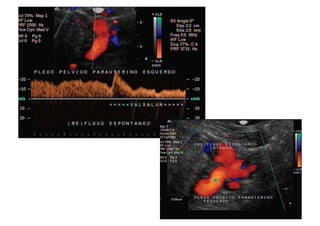

Refluxo  de  veia  Gonadal  com  formação   varicosa  ao  lado  do  ovário

Comment  établir  le  diagnos=que  ?   1.  Par   la   symptomatologie,   en   par8culier   la   douleur  et  la  lourdeur  dans  le  bassin  avec  une   aggrava8on   pendant   la   menstrua8on,   mais   aussi   la   dysménorrhée,   la   dyspareunie,   la   cons8pa8on  et  les  douleurs  lombaires.   2.  Par   la   présence   de   varices   dans   la   région   postérieure   et   latérale   des   cuisses,   dans   les   fessiers  et  les  par=es  génitales.   3.  À   l’aide   d’un   écho-­‐doppler   transvaginal   et   abdominal.